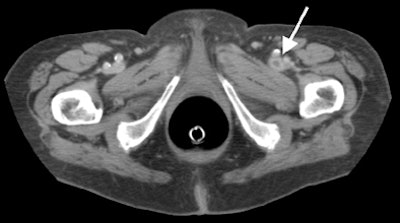

"This is an example of metastasis of ovarian carcinoma to the right psoas muscle," he said of a CT image projected on a screen. "In the same patient we can see thrombosis of the right femoral vein due to compression of this metastasis. The metastasis was successfully treated with surgery and femoral vein with heparin.... This is an example of an aortic aneurysm inflamed with an aortic duodenal fistula, which has been successfully treated in an emergency operation."

| A 76-year-old patient with thrombosis of the left femoral vein that was detected on IV contrast-enhanced CT colonography, and successfully treated with heparin. Image courtesy of Dr. Adrian Spreng and Dr. Hanno Hoppe. |